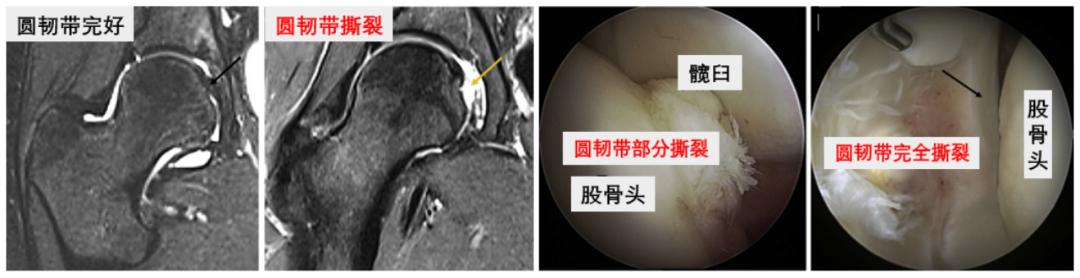

探查圆韧带,确认撕裂后,使用刨削、射频清理残端。

磁共振(MRI)及髋关节镜下的圆韧带损伤

髋关节镜下圆韧带清理术前术后对比③髋关节囊折叠紧缩缝合术